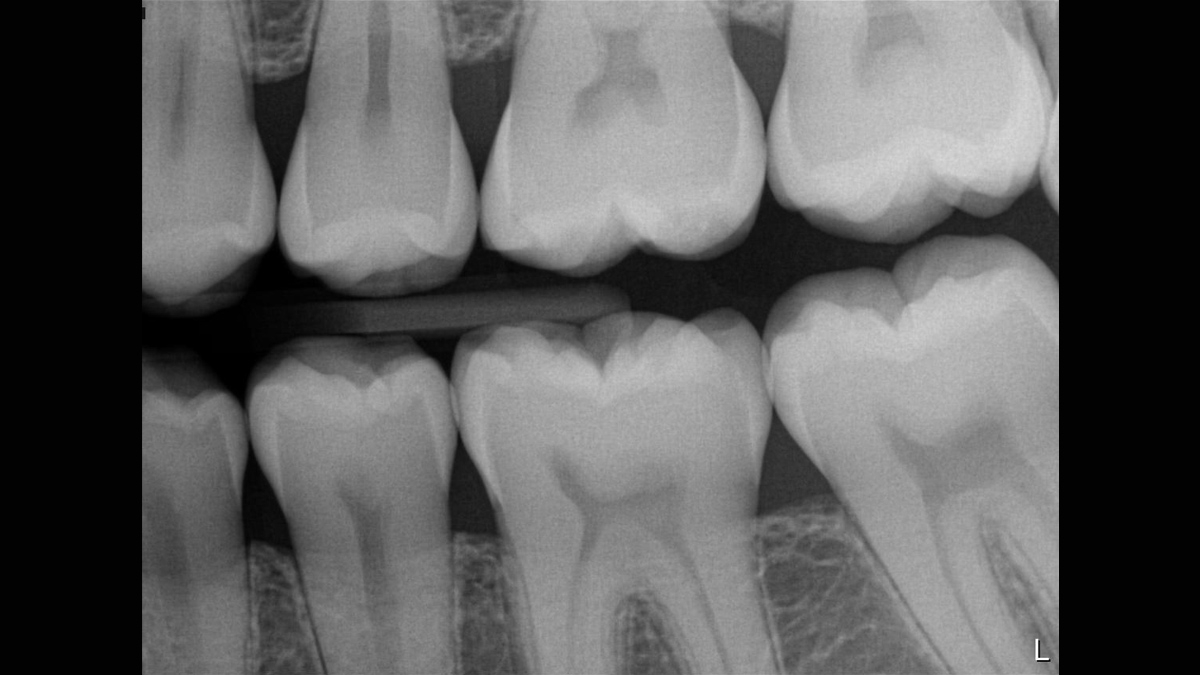

Los sensores intraorales de Dentsply Sirona proporcionan calidad de imagen de vanguardia que apoya el diagnóstico preciso del tratamiento y visión clara de la situación clínica. Respaldado por elecciones expansivas del sistema, mejora de filtro de imagen y servicio de vanguardia y personal de apoyo, los sensores intraorales Xios ofrecen varias posibilidades para su consultorio - brindándole beneficio a usted y sus pacientes.